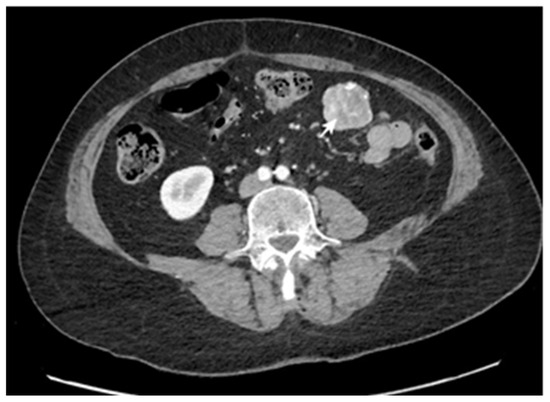

3. Results

3.2. Treatment Particularities